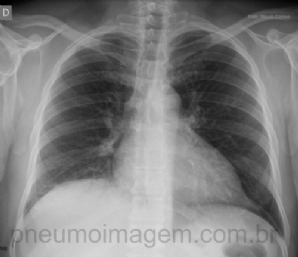

CASO CLÍNICO #6

Observe essa radiografia com essa massa paratraqueal à direita. Com base somente na incidência em PA, onde se localiza essa lesão? a) Pulmão b) Mediastino c) Caixa torácica Deixe seus comentários abaixo! ************ Please note that right paratrac...